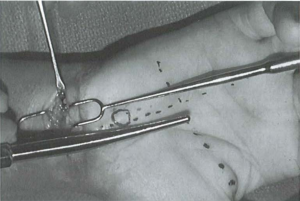

- Dùng cannula đưa vào vết mổ cổ tay, qua OCT, đưa qua vết mổ gan tay

Đưa cannula vào ống cổ tay